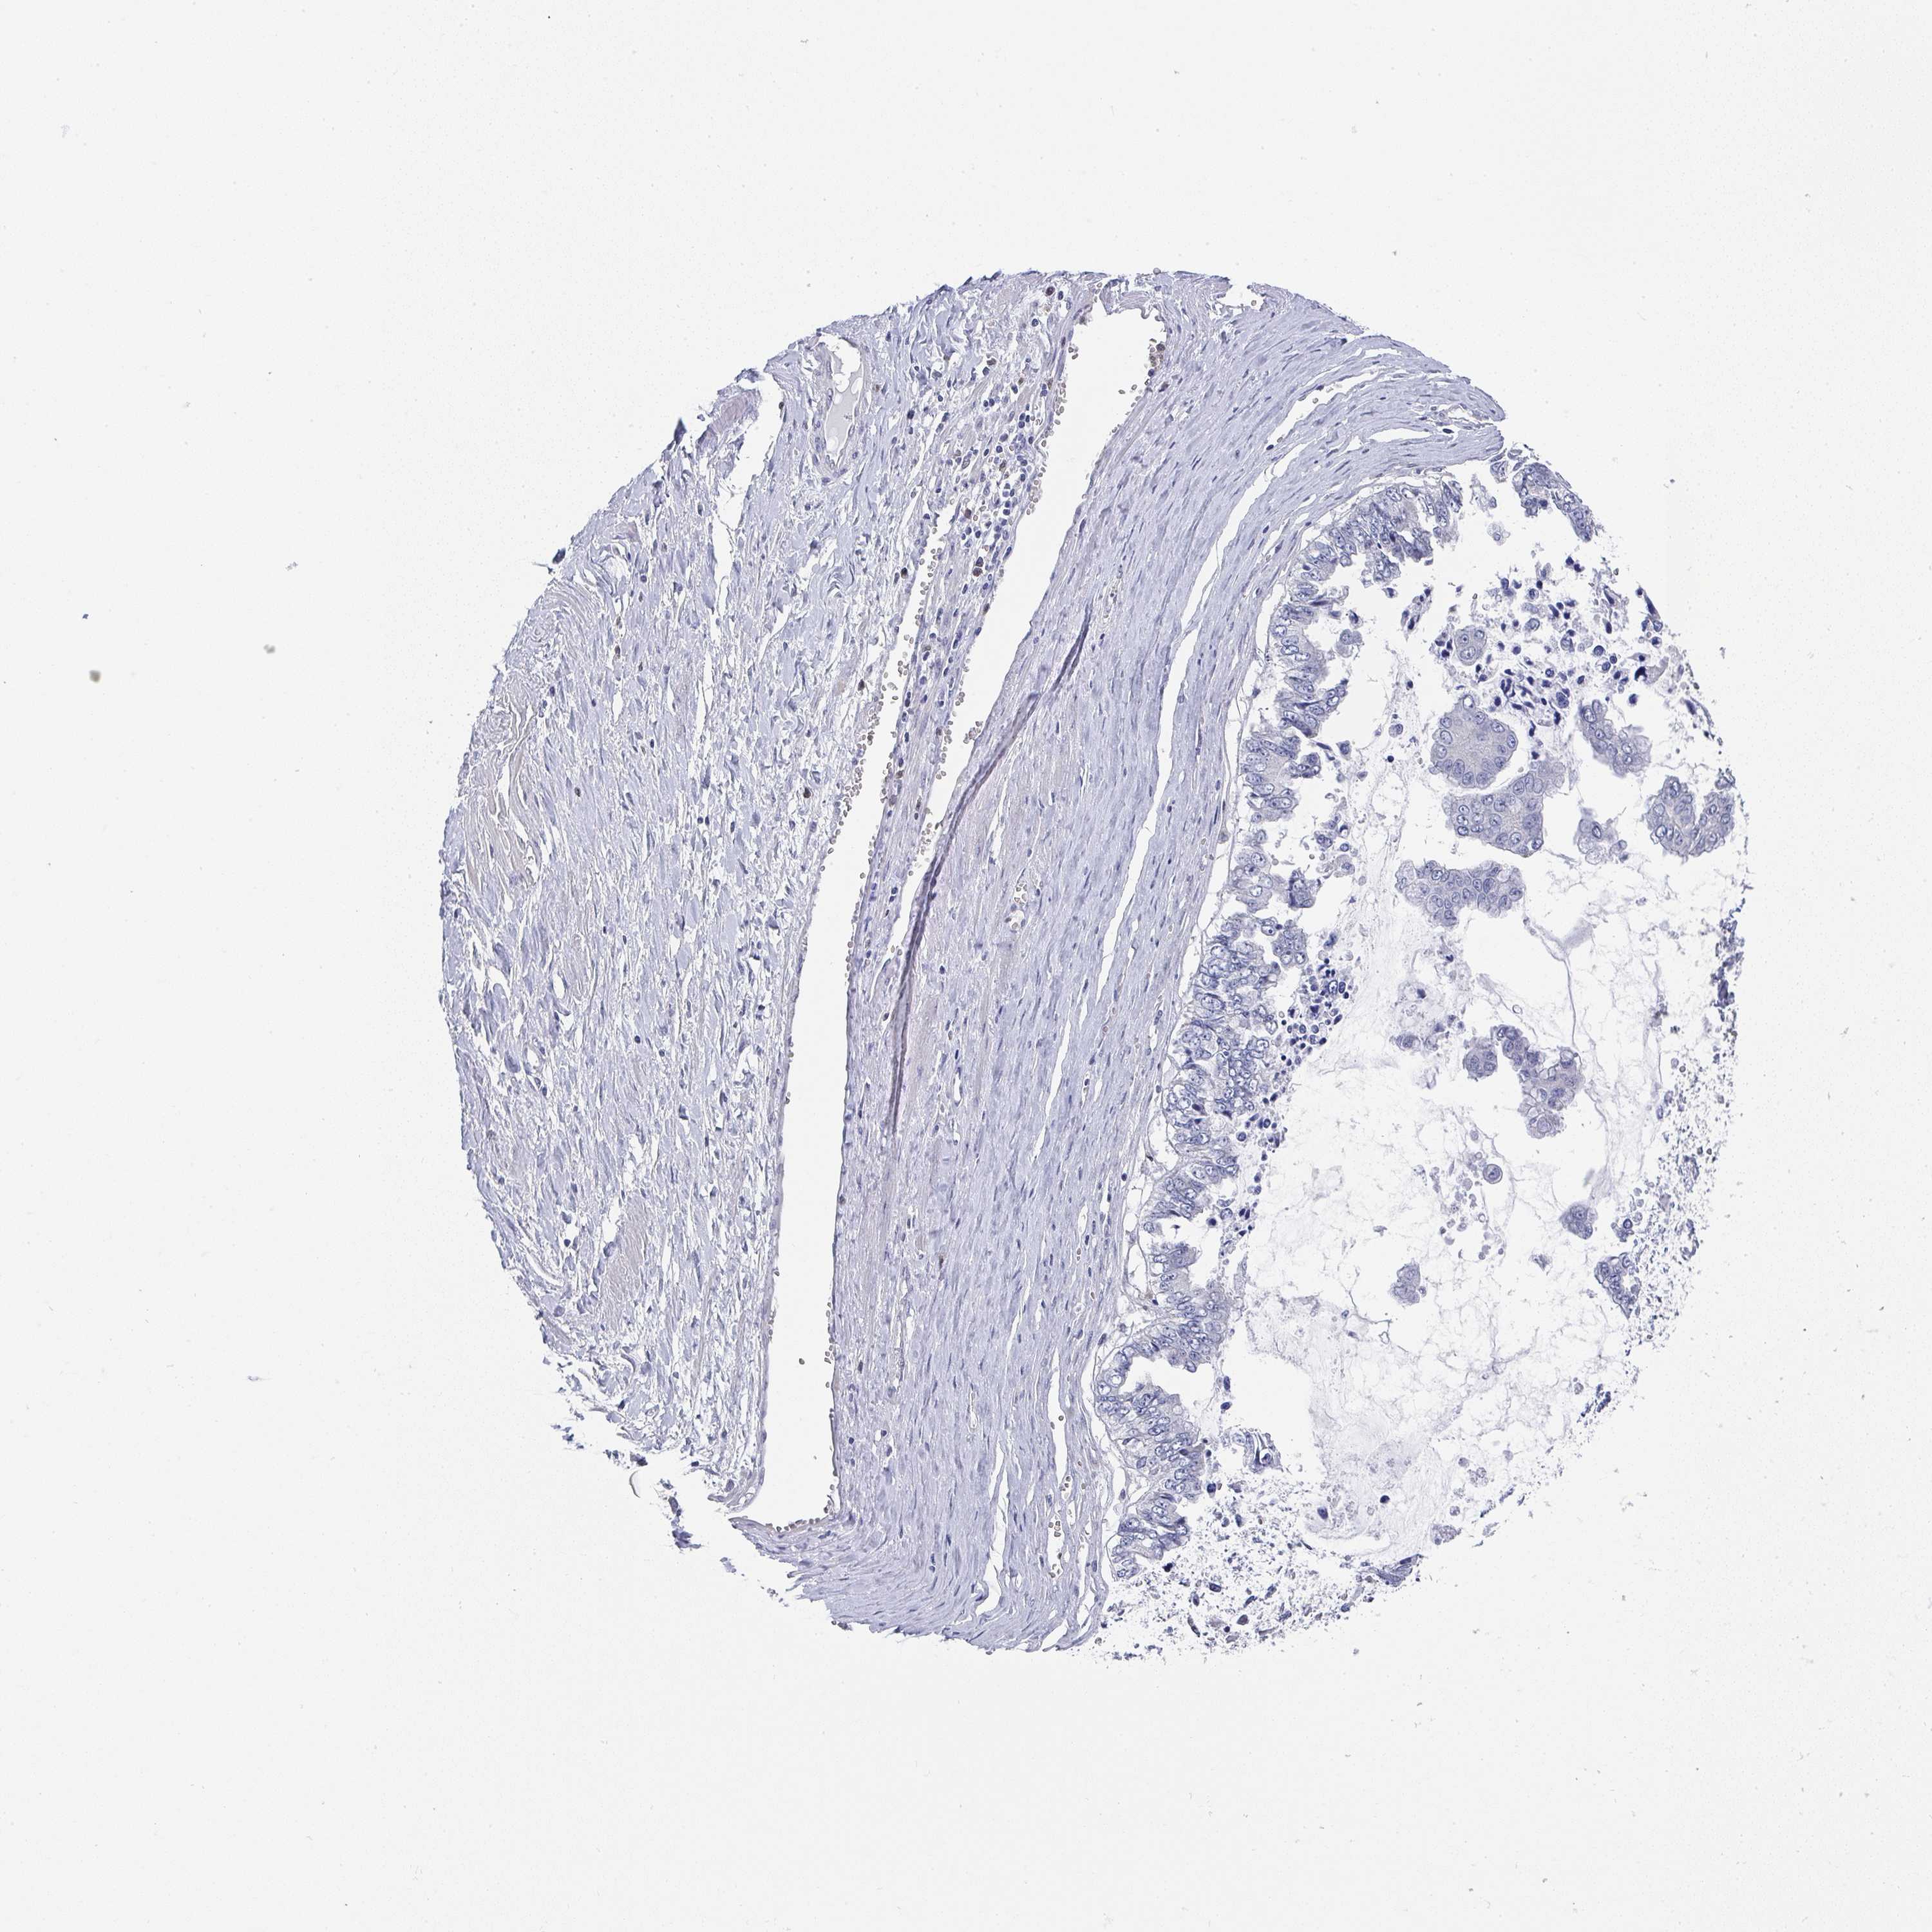

OVARIAN CANCER - Protein expressioni

A mouse-over function shows sample information and annotation data. Click on an image to view it in a full screen mode. Samples can be filtered based on level of antibody staining by selecting one or several of the following categories: high, medium, low and not detected. The assay and annotation is described here.

Note that samples used for immunohistochemistry by the Human Protein Atlas do not correspond to samples in the TCGA dataset.

Antibody stainingi

Antibody staining in the annotated cell types in the current human tissue is reported as not detected, low, medium, or high, based on conventional immunohistochemistry profiling in selected tissues. This score is based on the combination of the staining intensity and fraction of stained cells.

Each image is clickable and will lead to virtual microscopy that enables deeper exploration of all samples and also displays staining intensity scores, fraction scores and subcellular localization as well as patient and tissue information for each sample.

Antibody HPA047836

Antibody HPA052095

Antibody CAB004524

Cystadenocarcinoma, serous, NOS

Cystadenocarcinoma, mucinous, NOS

Carcinoma, endometroid